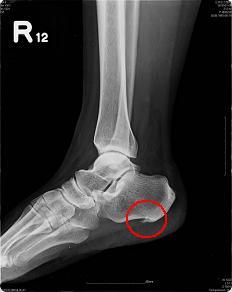

坐久了站起来时脚后跟痛,站久了走起来脚后跟痛,没有拉伤也没有扭伤,没有肿也没有破,为何脚后跟如此痛?不少中老年妇女在骨科门诊中或疼痛科门诊中常常会这样描述自己的困扰?倘若接受X光片照射,可以看到足跟部位出现了骨质增生,其余一切正常。其实,这是一种病症。学名叫"跟痛症"。

跟痛症是指多种足跟部疼痛综合症,主要指足跟底面疼痛,目前认为有跖腱膜炎、脂肪垫劳损、神经卡压等均可造成足跟痛,其中跟骨结节周围由慢性劳损所引起的以疼痛及行走困难为主的病症,主要是跖腱膜或跟腱附着处的慢性炎症。

跟骨是人体负重的主要部分,人体在站立时有50%以上的体重是由跟骨与距骨来承担的,中老年人,由于跟骨后内侧的骨质增生、跟骨脂肪垫的萎缩、跖腱膜的弹性减弱,加上骨质疏松,当长时间站立、行走时易诱发此病。跟痛症主要为足跟底部钝痛且持续,跟腱附着处也可肿胀、压痛。

手术治疗:进行关节镜下手术治疗,切除增生骨质。